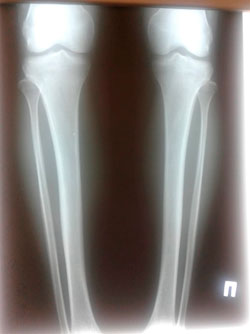

Исходник - 21 год.

Дата операции - 22.09.2020